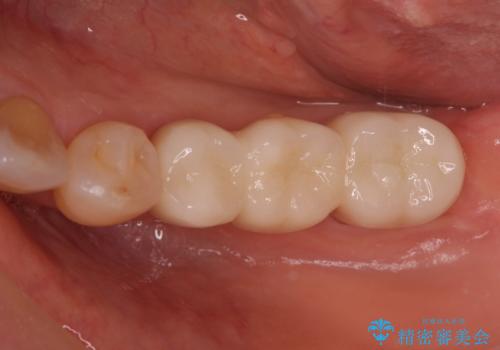

抜歯後に部分的にワイヤー矯正を半年ほど行ってから、ブリッジを入れる治療を行いました。

奥歯の部分矯正を行うことで、歯の傾きが良くなり、結果神経を取らずにブリッジを入れていくことができました。

通常矯正治療後は歯並びが戻らないように保定が必要ですが、ブリッジを入れているので歯並びは戻らないため保定が不要です。

部分矯正と補綴の相性は良いといえます。